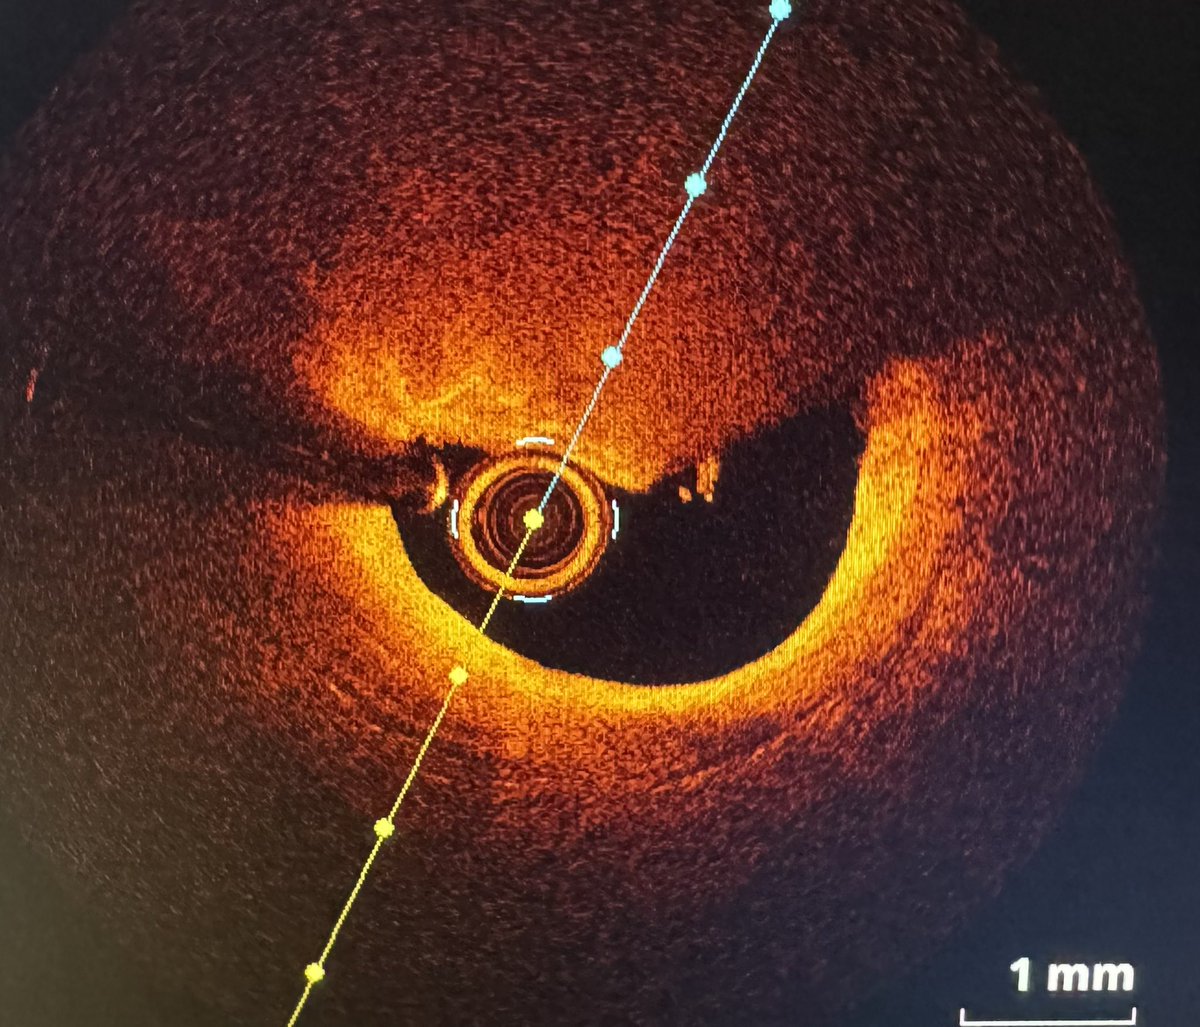

Este bichito 🐜 ha sacado @nicolasmmaneiro en la primera y única pasada en un paciente con un único 🫁 🚨En unos días se publican resultados del PEERLESS en el #TCT2024 !! @pabl0salinas @belcid7 @JuradoRomanAl @jmmoreiras @meucardial @maitevelazquezm 🤷🏻♂️¿Pronósticos?🤷🏻♂️